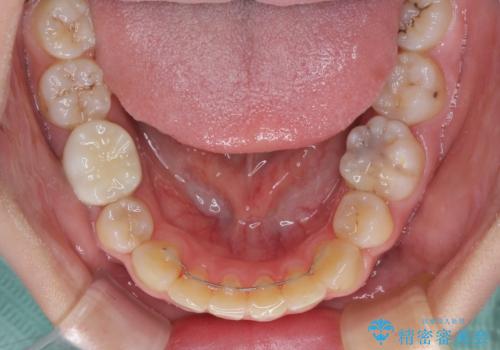

- ハーフリンガル

- 口元の突出感を気にして来院された患者様です。

上下左右の第一小臼歯4本を抜歯して口元を下げる治療計画としました。

目立たない装置が希望であったため、上顎が裏側装置である、ハーフリンガル装置を選択されました。

非常に大きな虫歯のあった下顎大臼歯は、根管治療を行い、矯正治療後にオールセラミッククラウンにて補綴治療を行いました。